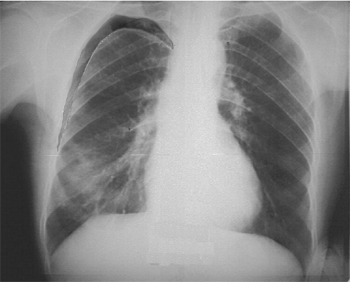

Рентгенологически: воздух в плевральной полости, выявляемый как зона отсутствия легочного рисунка по периферии грудной клетки в верхних отделах, ателектаз (спадение) легкого с четко очерченным краем, возможно смещение сердца в здоровую сторону (рис. 4).

Рис. 4. Пневмоторакс